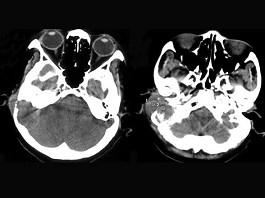

女,56岁,右侧中耳术后发现右外耳道新生物一年,PE:右外耳道内段被新生物充满,CT如图所示,应诊断为 ( )